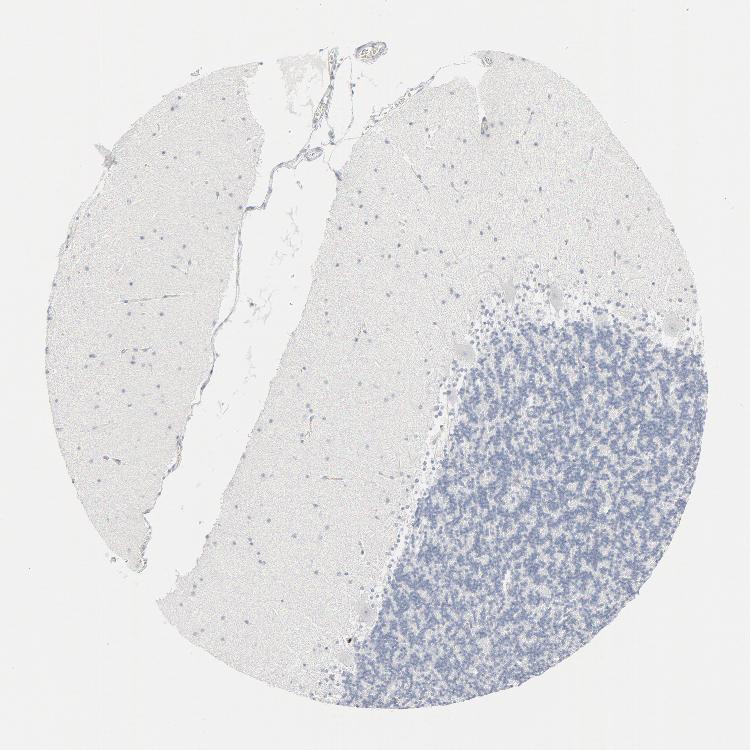

CEREBELLUM - Antibody stainingi

Antibody staining in the annotated cell types in the current human tissue is reported as not detected, low, medium, or high, based on conventional immunohistochemistry profiling in selected tissues. This score is based on the combination of the staining intensity and fraction of stained cells.

Each image is clickable and will lead to virtual microscopy that enables deeper exploration of all samples and also displays staining intensity scores, fraction scores and subcellular localization as well as patient and tissue information for each sample.

Antibody HPA003259Antibody CAB002578

Purkinje cells Not detectedNot detected

Cells in granular layer Not detectedNot detected

Cells in molecular layer Not detectedNot detected